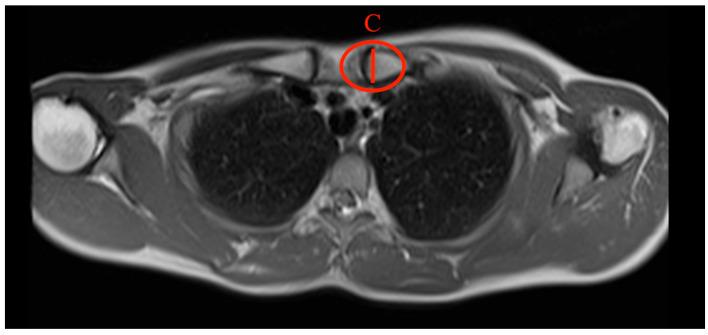

基于磁共振成像的胸锁关节和锁骨解剖结构的规范值:对1591名健康参与者的综合分析

The clavicle remains one of the most fractured bones in the human body, despite the fact that little is known about the MR imaging of it and the adjacent sternoclavicular joint. This study aims to establish standardized values for the diameters of the clavicle as well as the angles of the sternoclavicular joint using whole-body MRI scans of a large and healthy population and to examine further possible correlations between diameters and angles and influencing factors like BMI, weight, height, sex, and age. This study reviewed whole-body MRI scans from the Study of Health in Pomerania (SHIP), a German population-based cross-sectional study in Mecklenburg-Western Pomerania. Descriptive statistics, as well as median-based regression models, were used to evaluate the results. We could establish reference values based on a shoulder-healthy population for each clavicle parameter. Substantial differences were found for sex. Small impacts were found for height, weight, and BMI. Less to no impact was found for age. This study provides valuable reference values for clavicle and sternoclavicular joint-related parameters and shows the effects of epidemiological features, laying the groundwork for future studies. Further research is mandatory to determine the clinical implications of these findings.

尽管人们对锁骨及其相邻胸锁关节的磁共振成像了解甚少,但锁骨仍是人体中最易骨折的骨头之一。本研究旨在通过对大量健康人群进行全身MRI扫描,建立锁骨直径和胸锁关节角度的标准化值,并进一步研究直径、角度与BMI、体重、身高、性别和年龄等影响因素之间可能存在的相关性。本研究回顾了德国梅克伦堡-前波美拉尼亚州基于人群的横断面研究——波美拉尼亚健康研究(SHIP)的全身MRI扫描数据。采用描述性统计以及基于中位数的回归模型来评估结果。我们能够为每个锁骨参数建立基于肩部健康人群的参考值。研究发现性别之间存在显著差异。身高、体重和BMI的影响较小。年龄的影响较小或几乎没有影响。本研究为锁骨和胸锁关节相关参数提供了有价值的参考值,并显示了流行病学特征的影响,为未来的研究奠定了基础。必须进行进一步的研究以确定这些发现的临床意义。